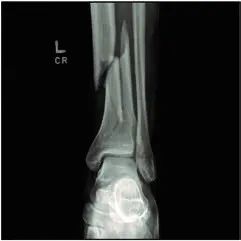

1.切口负压治疗与标准伤口敷料对严重创伤合并下肢骨折术后深部手术部位感染的影响: WHIST随机临床试验(JAMA 2020; 323:519–26)

85%的严重创伤患者存在严重的肢体损伤,其中骨折最常见。严重创伤引起的全身性炎症反应合并骨折临近部位的软组织损伤,可导致伤口深部感染。

本研究比较了伤口负压治疗与标准敷料覆盖在降低严重创伤性下肢骨折手术相关的伤口深部感染率方面的效果。

随机选取1548名患者(平均年龄50岁),其中有1519名(98%)患者的主要结果数据可纳入研究。

术后30天深部手术部位感染率无明显差异。在伤口负压治疗组中30天深部伤口感染率为5.84%(770例中有45例),而在标准敷料组中感染率为6.68%(749例中有50例)(OR 0.87 [95% CI,0.57-1.33];绝对风险差异ARD -0.77% [95% CI,–3.19-1.66%];P = 0.52)。

对实际应用的敷料类型的方案数据分析得出了类似结果:伤口负压治疗组的感染率为6.14%,而标准敷料组的感染率为6.57%(OR 0.93 [95% CI,0.6 -1.44];ARD 0.33% [95% CI,–2.93-2.15%];P = 0.76)。术后90天感染率两组间也无差异。

(文章选择:Martin J. London;图片:J. P. Rathmell)

关键信息:该研究提示,针对因严重创伤导致的下肢骨折而接受手术的患者,伤口负压治疗与标准敷料覆盖针对深部手术部位感染方面并无显著差异。